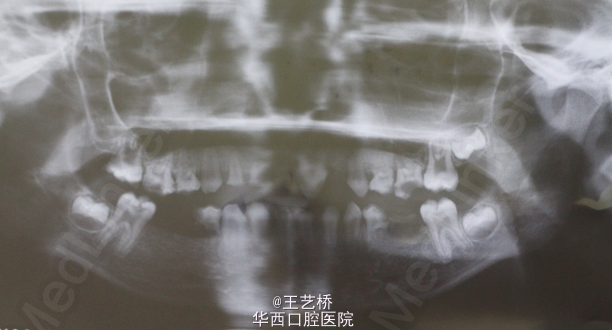

从来没有想过一个11岁的小朋友牙齿情况会是这样,在深深惋惜的同时一个巨大的问题接踵而至:我们该怎么对这个患者进行治疗呢?评估之后能够保留的牙齿我们可以进行根尖诱导或者根管治疗,但是小朋友的咬合问题应该怎么解决呢?11岁就进行修复治疗肯定是不行的,需要现在开始维持修复间隙吗?如何维持?更加亟待解决的是小朋友的咀嚼问题,能暂时使用可摘义齿恢复咀嚼吗?